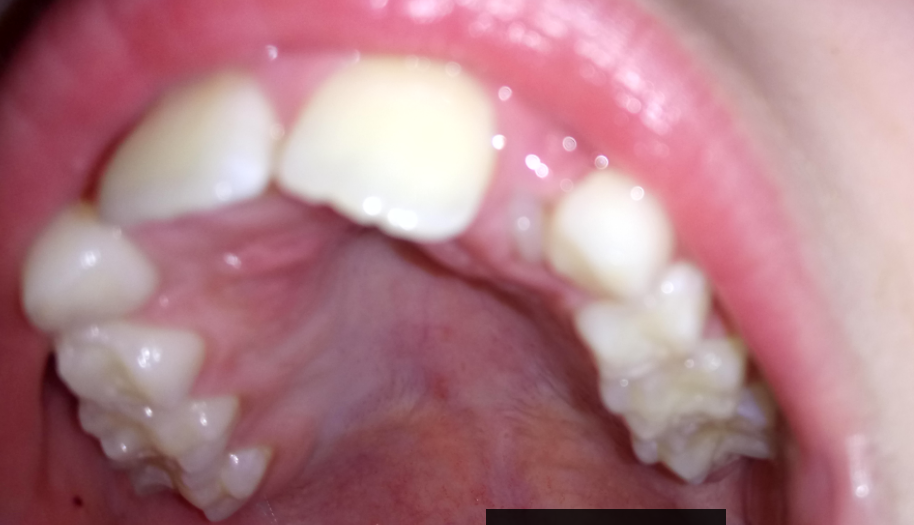

Unterschied von Milchzähnen zu bleibenden Zähnen Meist tritt dieses Phänomen bei den Schneidezähnen auf. Zwischen dem sechsten und achten Lebensjahr beginnen in der Regel die Milchzähne auszufallen und die bleibenden Zähne wachsen nach Solche haifischzähne treten vor allem an den unteren Schneidezähnen auf

Zahnfehlstellungen Arten, Ursachen & Korrekturkosten . Haifischzähne entstehen, wenn der neue Zahn direkt hinter oder vor dem Milchzahn wächst, ohne die Wurzel des Milchzahns aufzulösen und ihn da durch herauszudrücken Die Ursachen können genetisch bedingt sein oder einfach Zufall.

Zahnfehlstellungen Arten, Ursachen & Korrekturkosten . Am häufigsten taucht die Auffälligkeit Doppelzahn bei den. Wenn ein neuer Zahn neben einem Milchzahn wächst, ist das in den meisten Fällen völlig normal und harmlos